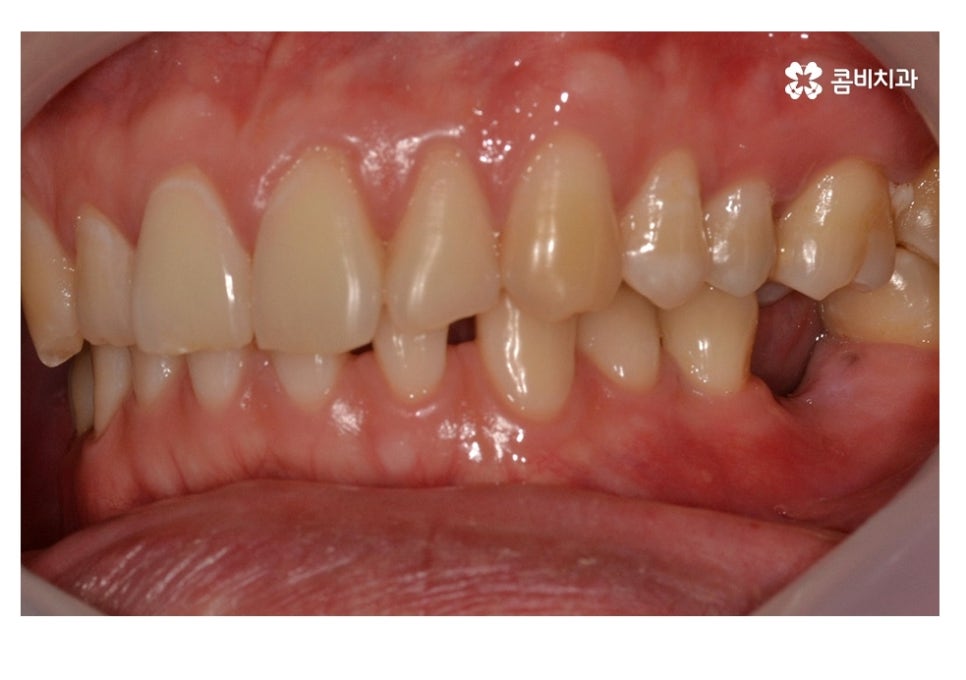

치아교정은 흔히 치아의 심미성을 위해서 치료를 진행한다고 알고 계시겠지만

부정교합이나 불규칙한 치열은 충치 및 잇몸질환이 발생할 수 있는 가능성을

높이며 부정교합이 심한 경우에는 나이가 들수록 턱관절 장애나 소화 불량 등의

전신 건강에도 안 좋은 영향을 줄 수 있으며 치열 상태는 얼굴형 및 골격에도

많은 영향을 주기 때문에 치열은 심미성 뿐 아니라 건강과 교합 등에도 밀접하다고 할 수 있어요.

치아가 벌어진 경우에는 치아 사이에 이물질이 더욱 쌓이기 쉽고

치석 관리를 좀 더 신경 써야 하기 때문에 치아교정을 통하여

심미성의 개선과 함께 치아 건강에도 향상에도 도움이 될 수 있어요.